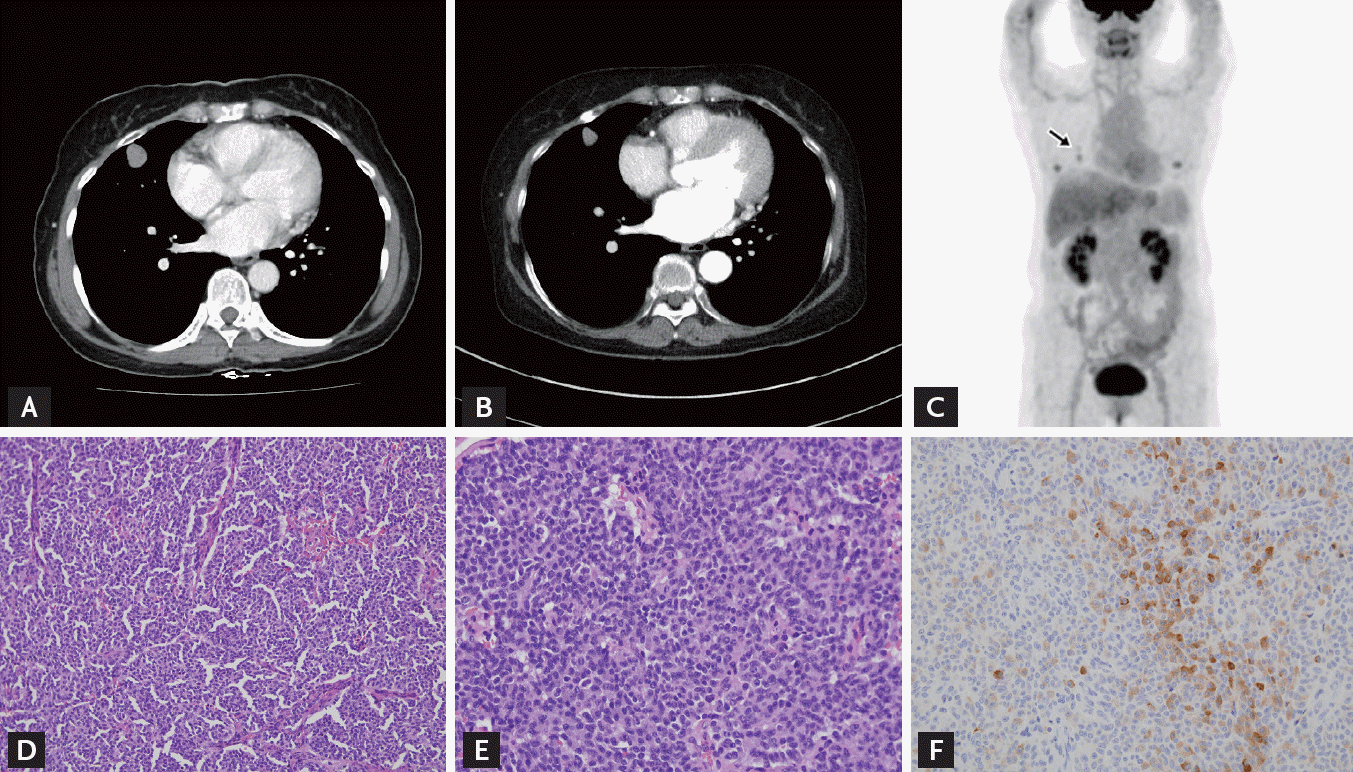

A 45-year-old woman was admitted to our clinic with a past medical history of hypertension (9 months) and a typical cushingoid appearance, which had become apparent 6 months earlier. She had a 2 cm lung nodule, which was considered as a sclerosing hemangioma by radiologic and clinical findings. Computed tomography (CT) showed a well-defined nodule with mild enhancement. There was no calcification and fat component within the nodule. This solitary lung nodule had remained unchanged for 7 years (Fig. 1A). On physical examination, she had a moon face, central obesity, and diffuse ecchymoses on her entire body.

The results of basal endocrinological examinations were summarized in Table 1. Pituitary magnetic resonance imaging (MRI) scan was normal. CT scans of her chest, abdomen, and pelvis were normal except for the 2 cm lung nodule (Fig. 1B). Endoscopy and colonoscopy examinations were also conducted, but had nonspecific findings. She underwent a successful IPSS without complications, which revealed a petrosal/peripheral ACTH ratio of 1.10 (Table 2). IPSS showed no central to peripheral ACTH gradient and lateralization. A positron emission tomography (PET)-CT scan was performed and increased metabolic activity was detected on the lung nodule (maximum standardized uptake value, 1.7) (Fig. 1C).

We concluded that the ectopic ACTH syndrome was associated with the lung nodule and decided to perform lung nodule biopsy. However, the patient did not consent due to the bleeding risk from the hemangioma and only agreed to resection of the lung lesion. She accordingly received a wedge resection with video-assisted thoracoscopic surgery. Histology showed a typical carcinoid tumor. Immunohistochemistry stains were positive for ACTH, CD56, synaptophysin, and thyroid transcription factor-1 (Fig. 1D-1F). Following resection of lung lesion, plasma levels of ACTH and cortisol decreased significantly (preoperative ACTH 251.69 pg/mL, cortisol > 50.0 µg/dL; postoperative ACTH 5.59 pg/mL, cortisol 1.76 µg/dL). She experienced general weakness post-surgery, and moon face progressively resolved. She received replacement steroid i.e., hydrocortisone 10 mg in the morning and 5 mg in the evening. Three month after surgery, we rechecked ACTH/cortisol (ACTH, 2.84 pg/mL; cortisol, 0.32 µg/dL). She no longer felt general weakness.